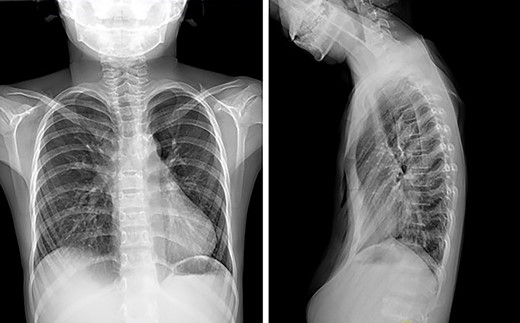

The patient was a 7-year-old boy. Two years ago, he underwent surgical treatment for pectus excavatum in a local hospital. At that time, Wang procedure was used and a steel bar was implanted. After the operation, the steel bar was displaced and the depression recurred (Figs 1 and 2), so the steel bar had to be taken out 1 year after the operation. After removal, his anterior chest wall still had obvious depression, and there was a tendency to aggravate. In order to completely correct the deformity, the patient was recently admitted to our hospital for surgery. Preoperative physical examination showed that the anterior chest wall was asymmetrically depressed, and the deepest depression was located in the right chest wall (Fig. 3). There was a scar in the middle of the anterior chest wall (Fig. 3). Preoperative imaging examination showed that the anterior chest wall was depressed, the heart was obviously compressed and moved to the left (Fig. 4). The operation was performed under general anesthesia. Supine position was adopted, with abduction of both upper limbs. Two incisions were made on both lateral chest wall respectively, which were located at the deepest plane of the depression. The muscles were dissected to expose the ribs in the incision. The depression was eliminated by Wung procedure, which was performed as follows [2]: A tunnel at the deepest plane of the depression was made. A special guider was inserted directly through the gap between the sternum and the heart, and then a steel bar introducing tube was connected with the guider. After the introducing tube was pulled into the body by the guider, a special steel bar was pulled by the introducing tube to the bottom of the depression. After the steel bar was rotated, the depression was supported, but the left chest wall began to be protrusive. In order to make the anterior chest wall more beautiful, Wenlin procedure was performed next [3, 4]. An incision at the median scar was made, and a tunnel was built from the median incision to the incision on both sides, which was located between the bone structures and the chest wall muscles. The second steel bar was inserted into the tunnel. After the protrusive part of the anterior chest wall was pressed with the middle part of the steel bar, both sides of the bar was fixed to the ribs on the lateral chest wall. Drainage tubes were placed in the thoracic cavity on both sides, the incision was closed, and the operation was completed (Fig. 5). No complications occurred during the operation. The total operation time was 50 min and the intraoperative bleeding volume was 5 ml. Postoperative X-ray examination showed that the positions of the steel bars were satisfactory and the shape of the chest wall was basically normal (Fig. 6). The patient was discharged 5 days after operation. Follow up for 1 month showed no change in thoracic shape and no discomfort.